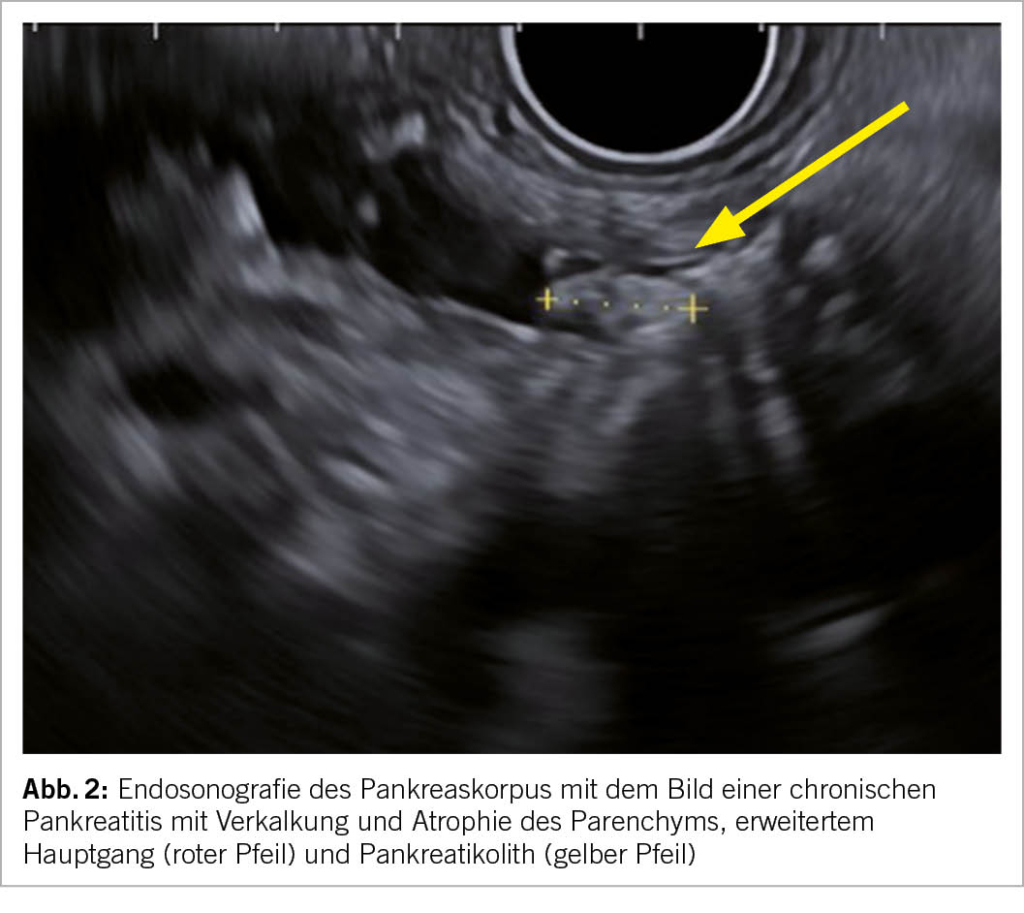

Die Bildgebung ist eine der wichtigsten Bestandteile der Diagnostik. Die Verfahren der Wahl mit hoher Spezifizität und Sensitivität sind die Endosonografie (Endoskopischer Ultraschall, Abk. EUS, Bild 2), die Computertomografie (Abk. CT, Abb. 3) und die Magnetresonanztomografie (Abk. MRI). Die transabdominale Sonografie kann das Pankreas leider häufig nur ungenügend darstellen, dient aber als kostengünstige und breit verfügbare initiale Untersuchung. Die Zeichen der chronischen Pankreatitis bestehen u.a.

aus einem erweiterten, irregulären Hauptgang, Pankreatikolithen (Abb. 2), Verkalkungen (Abb. 3), hyperechogene Foci und Septen, lobuliertes Parenchym, Atrophie (Abb. 3) und ev. lokale Komplikationen (Tab. 1).

Alle bildgebenden Methoden haben ihre Vor- und Nachteile und sollten idealerweise mit einer Fachperson je nach Fragestellung vorbesprochen werden, um Doppeluntersuchungen zu vermeiden. Die EUS eignet sich v.a. zur Detektion früher Stadien der chronischen Pankreatitis. Suspekte Befunde können diagnostisch punktiert werden und lokale Komplikationen wie Pseudozysten oder Walled-off Nekrosen können endoskopisch behandelt werden. Die CT stellt Kalk (Abb. 3) äusserst zuverlässig dar. Falls der Verdacht auf Pankreaskarzinom besteht, sollte zwecks Beurteilung der Resektabilität ein spezifisches Pankreasprotokoll sowie eine Thorax-CT angemeldet werden. Das MR empfiehlt sich mit dem MRCP Zusatzprotokoll, um den Gallen- und Pankreasgang darzustellen.